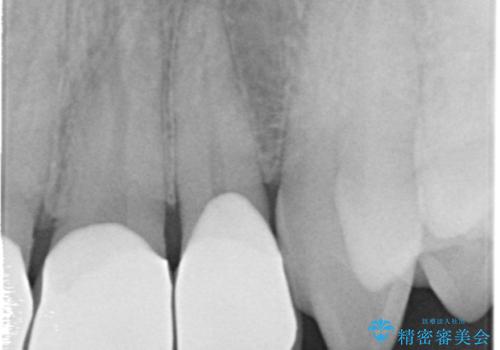

- 前歯のすき間を気にして来院。

矯正治療か、セラミックで最短で治すかの選択肢を提示し、セラミックで治すことにしました。

利点は、早く終わる上に、保定の必要がないため負担が少ないことが挙げられます。

ただし、セラミックは欠ける特性があるため、夜はナイトガードを使用していただくことにしました。

全て神経は取らずに、削りました。

長年コンプレックスだったすき間が閉じたとのことで、喜んでいただきました。